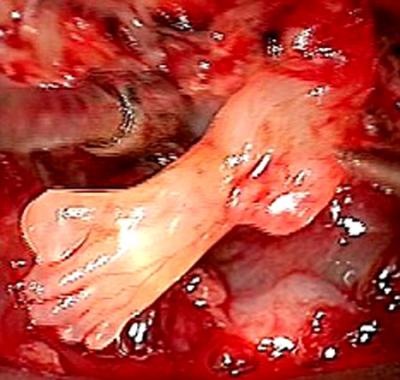

ان الدكتور بول غراب الذي يعمل في مستشفى “ميموريال” للأطفال في منطقة كولورادو سبرنينغز, اكتشف قدم في دماغ الرضيع سام إيسكويبيل خلال عملية لاستئصال ورم فيه, مشيرا إلى أنه وجد أيضا جزءا من الأمعاء قام باستئصاله. وأضاف ان العملية الجراحية التي أجريت للطفل في الثالث من أكتوبر الماضي تكللت بالنجاح.

إلى ذلك , وصف أطباء حالة الطفل بالنادرة, وبأنها أغرب حالة في تاريخ الطب البشري. وكانت أجريت للام فحوصات التصوير ما فوق السمعي عندما كانت في الأسبوع الـ 41 من الحمل , وعندما تبين أن جنينها يعاني من خلل في الدماغ تقرر إجراء عملية فورية لتوليدها. يشار إلى أن الطفل يعيش الآن مع والديه وهو بخير حسبما ما يقول الأطباء